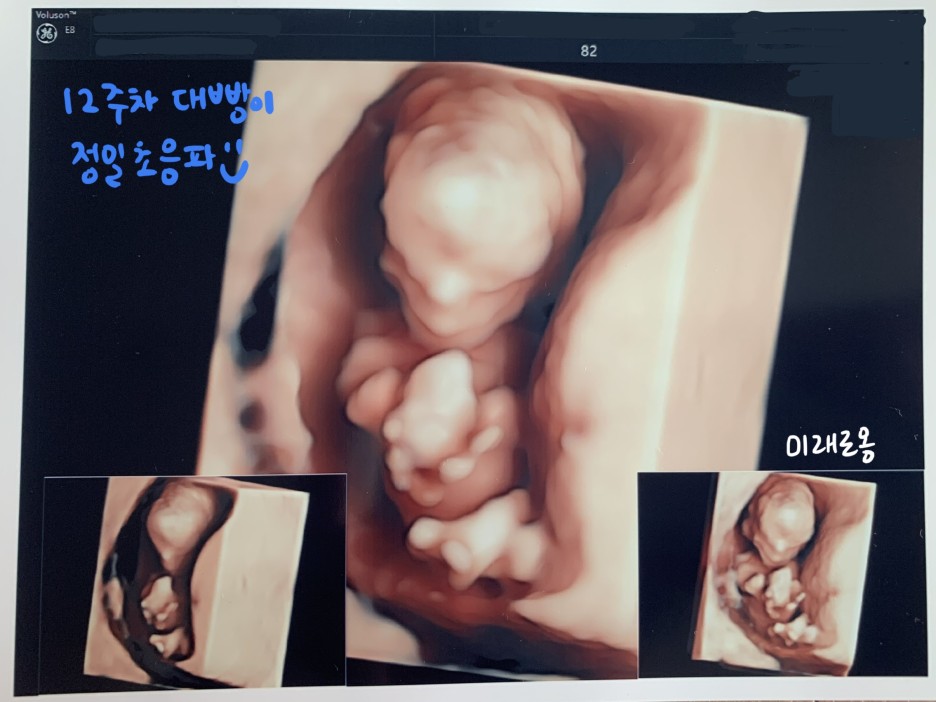

① 정밀초음파 검사 (목투명대 검사)

정밀 초음파 검사 (목투명대 검사)

지금까지는 질식초음파로

초음파 검사를 했었는데,

정밀초음파에서는 복부초음파가 진행되었다.

어쨌든 12~24주차에 진행하는

정밀초음파에서 가장 중요한 것은

바로 '태아 목투명대 검사'이다.

* 태아 목투명대 검사란?

태아의 뒷목과 피부 아래 투명대 사이의 두께,

즉, NT (Nuchal Translucency)를 측정해서

3mm 이상이 나오면

다운증후군 고위험군으로 분류된다.

다행히 대빵이는

목투명대가 0.59 mm 로 나와

정상 판정을 받았다.